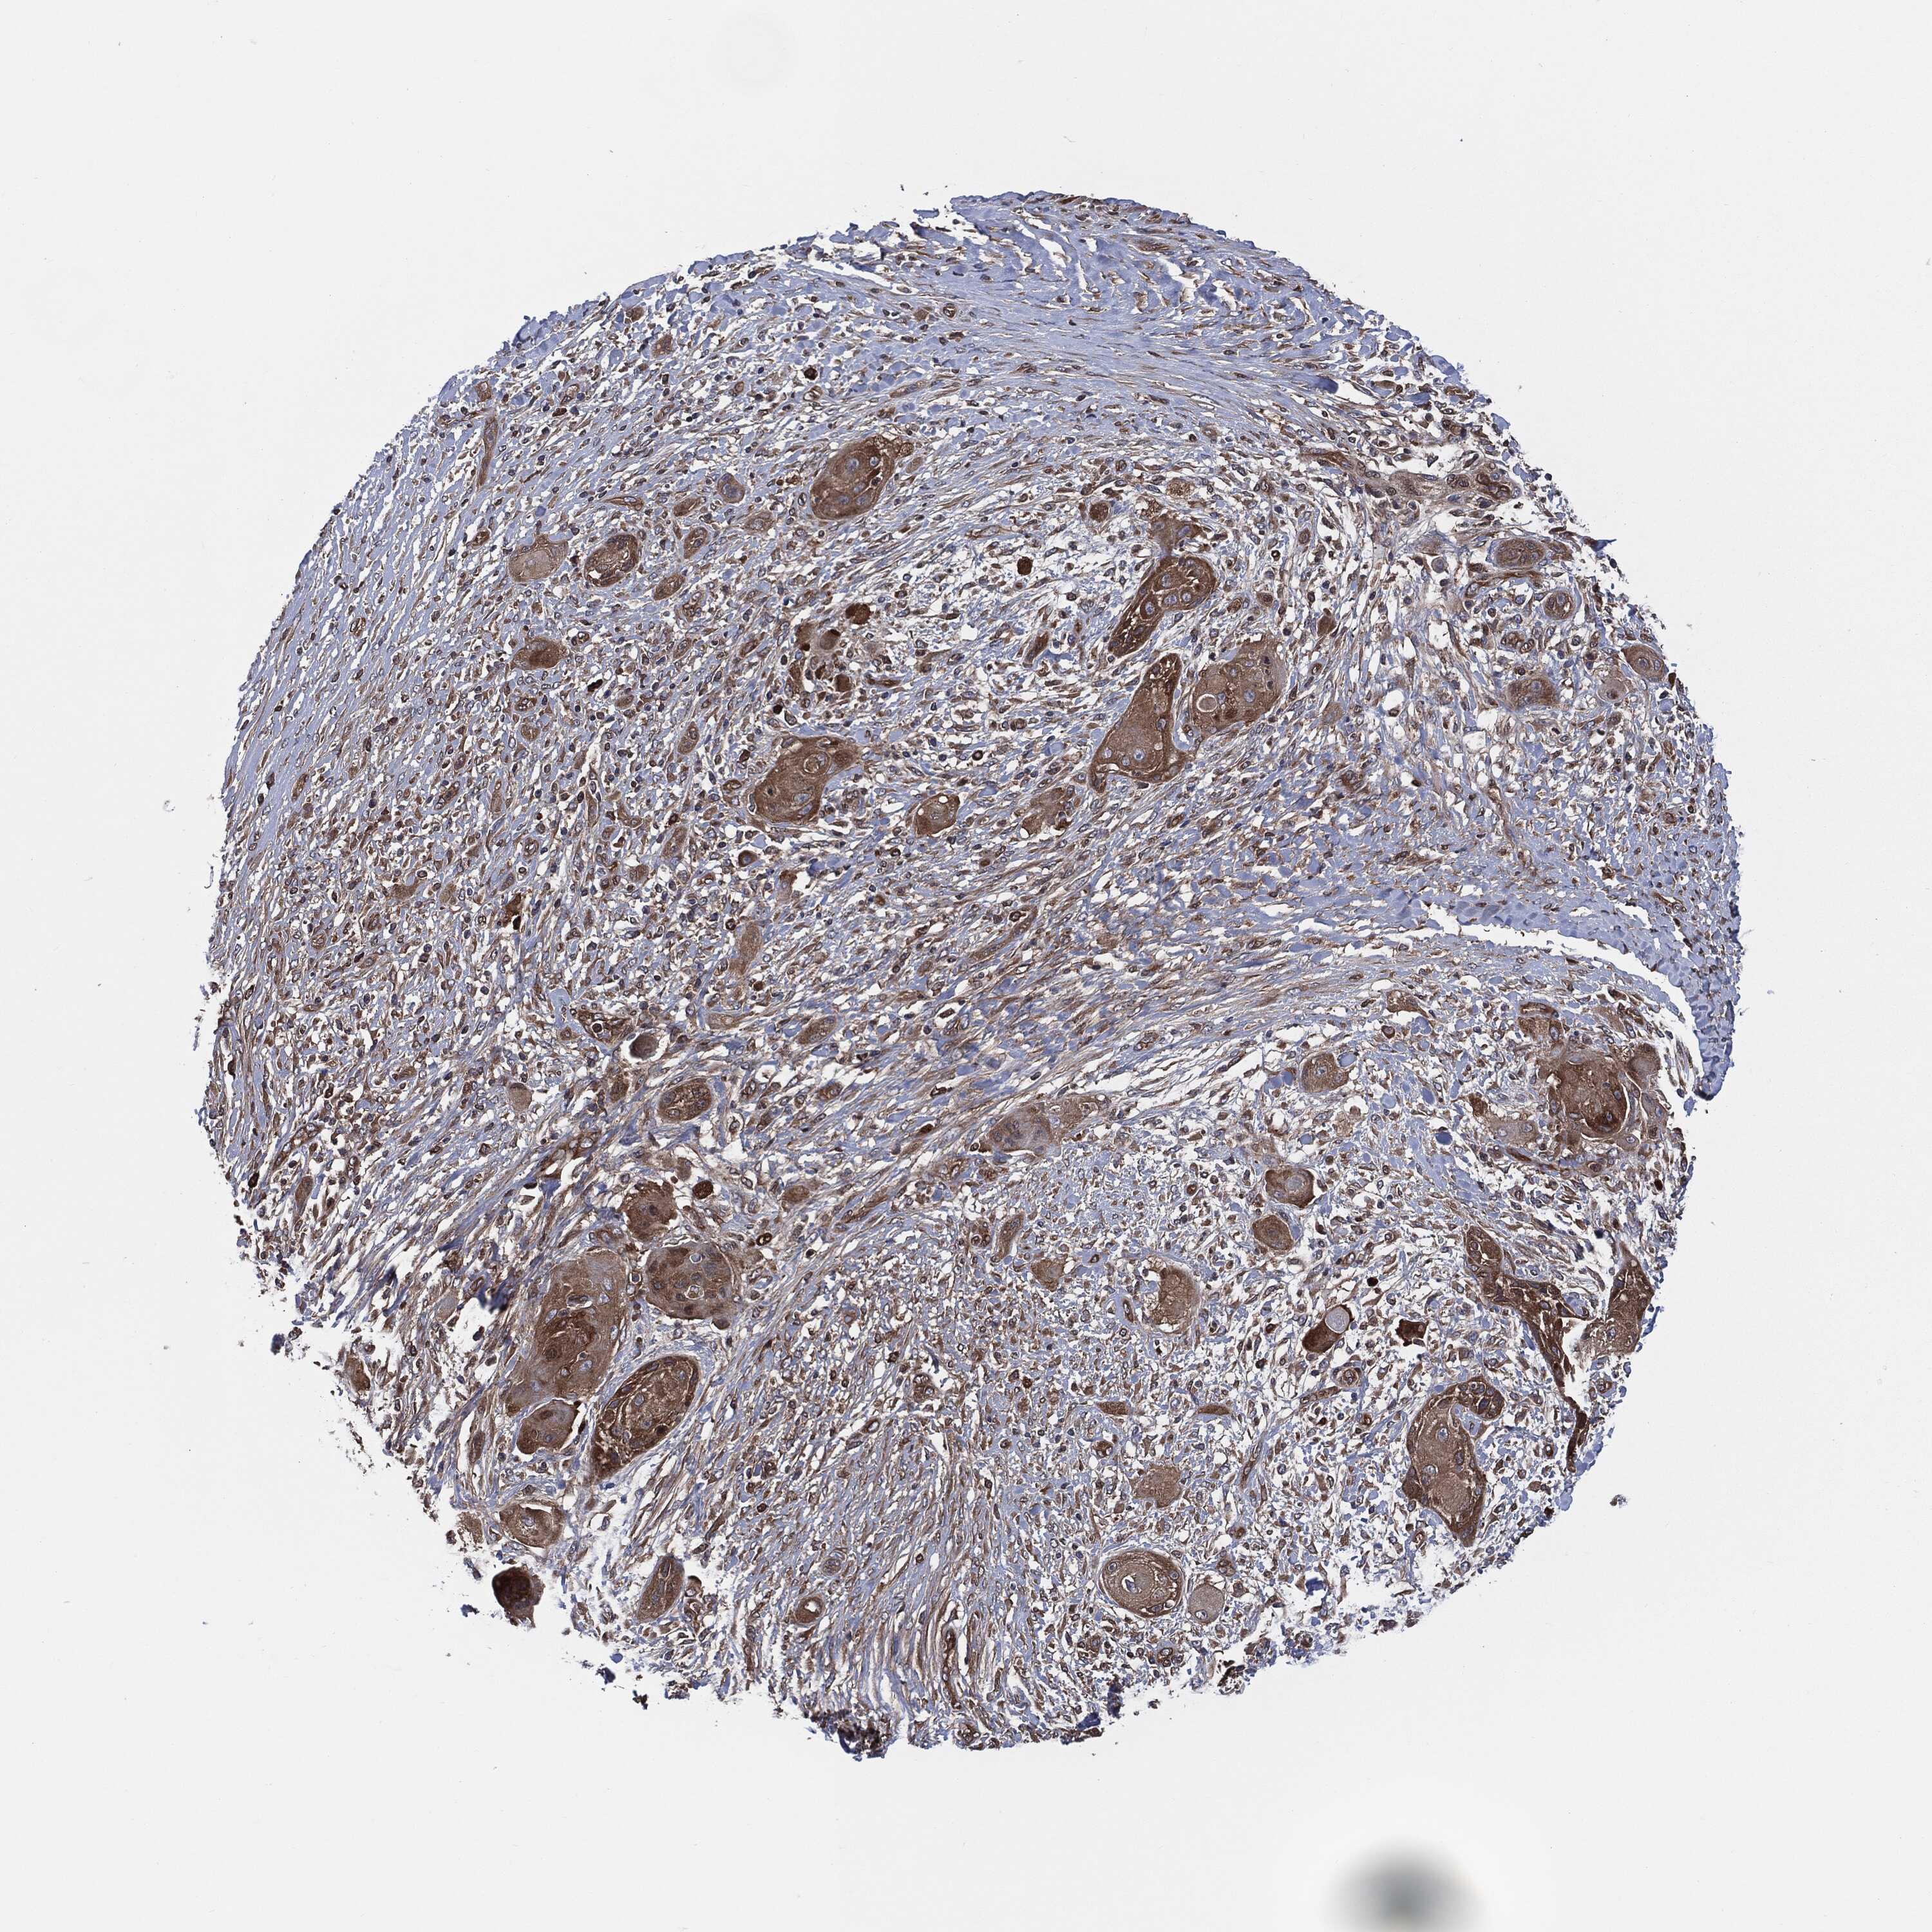

SKIN CANCER - Protein expressioni

A mouse-over function shows sample information and annotation data. Click on an image to view it in a full screen mode. Samples can be filtered based on level of antibody staining by selecting one or several of the following categories: high, medium, low and not detected. The assay and annotation is described here.

Antibody stainingi

Antibody staining in the annotated cell types in the current human tissue is reported as not detected, low, medium, or high, based on conventional immunohistochemistry profiling in selected tissues. This score is based on the combination of the staining intensity and fraction of stained cells.

Each image is clickable and will lead to virtual microscopy that enables deeper exploration of all samples and also displays staining intensity scores, fraction scores and subcellular localization as well as patient and tissue information for each sample.

HPA030419

HPA030420

HPA030422

CAB025196

CAB080286

CAB080287

Basal cell carcinoma

Squamous cell carcinoma, NOS

Squamous cell carcinoma, metastatic, NOS